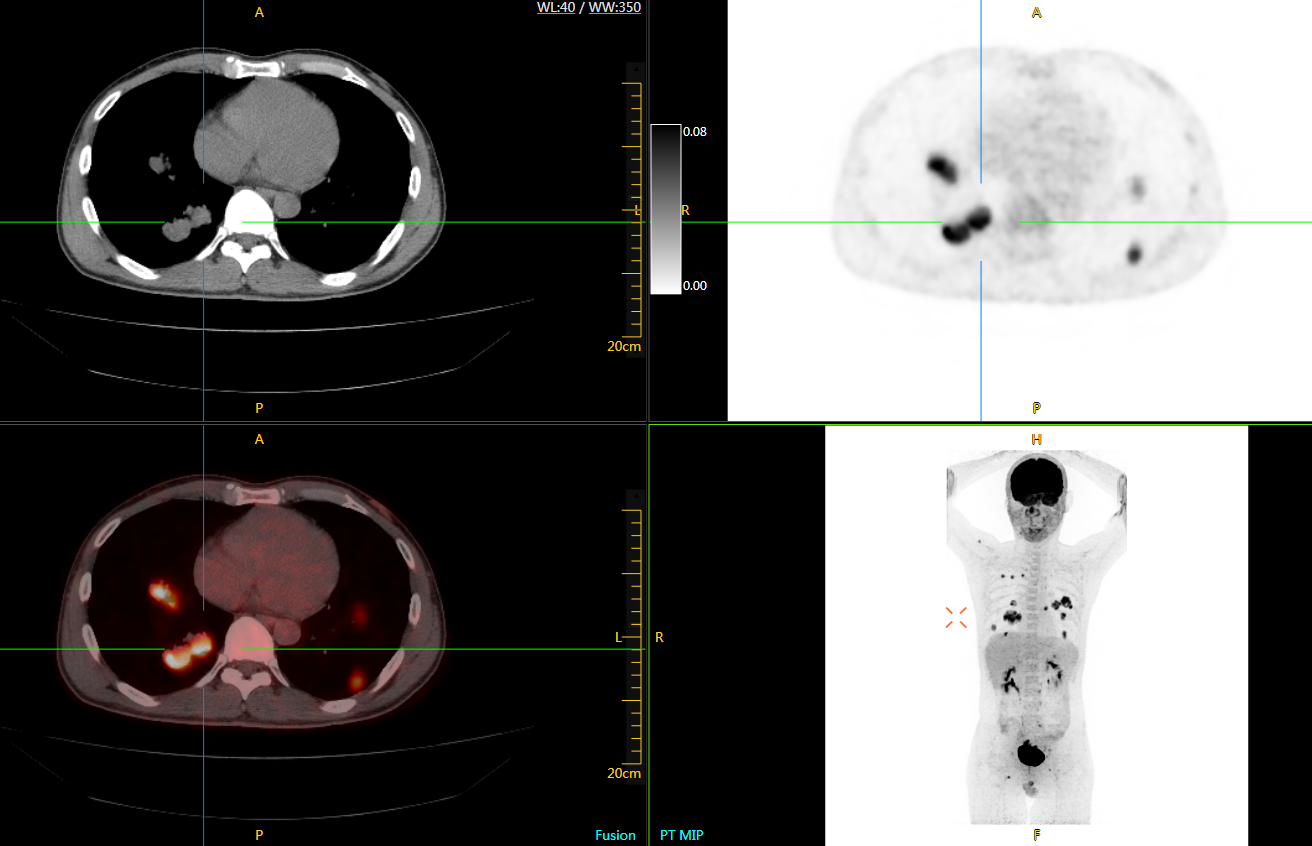

圖例

uExplorer探索者不再局限于傳統(tǒng)靜態(tài)代謝過(guò)程3D成像,而是在此基礎(chǔ)上新增一個(gè)維度——時(shí)間,從而實(shí)現(xiàn)4D全景成像。

注射總劑量為7.8mCi,14分鐘全身采集時(shí)間,在擁有超高靈敏度與超高分辨率的uEXPLORER上,即可得到展示顯示人體諸多精細(xì)結(jié)構(gòu)的高清三維圖像。

注射總劑量為7.8mCi,注射后1.6小時(shí),基于uEXPLORER探索者掃描1分鐘的圖像

注射總劑量為0.67 mCi FDG(低于常規(guī)劑量的十分之一),基于uEXPLORER探索者掃描15分鐘的圖像

注射總劑量為6.9mCi,注射后10小時(shí),基于uEXPLORER探索者掃描14分鐘的圖像